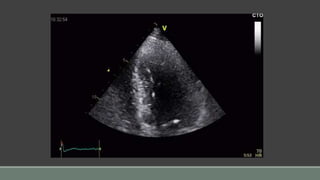

• #7 Instead, you think that the best tool for the job might be an echo. Whether it is a TOE or a transthoracic doesn’t really matter. In many cases, the conclusion will be fairly obvious with little controversy. Like here on those loops, where the RV looks very dilated, much bigger than the LV, poorly function, with a paradoxicum septum.

• #8 But in many cases, it will not be that obvious and we will end up saying… well… it looks sluggish… maybe sluggish ++. In fact, there is quite a bit of uncertainty and the little cat on the left side of the slide seems much less confident than before. We have to make a lot of assumptions and rely on rather indirect parameters to estimate ventricular function. We look at 2D areas and have to make estimates of volumes, then we estimate volume changes and take that as a good measure for contractility. And at the same time, we have knowledge of what the ideal volume for a particular patient would be and where he is at on the starling curve. So we end up summarizing the different indirect parameters by simply eyeballing the 2D picture. This means using a personal reference library in our own memory, created from previously seen echos in different clinical situations. So presumably, intensivists will have a slightly different interpretation than cardiologists for contractility for example, because a normal contractility in shocked patients is different to what is seen in ambulatory cardiology rooms.